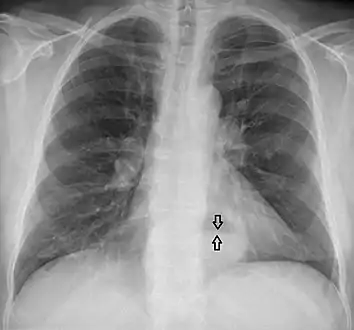

This hiatal hernia is mainly identified by an air-fluid level (labeled with arrows).